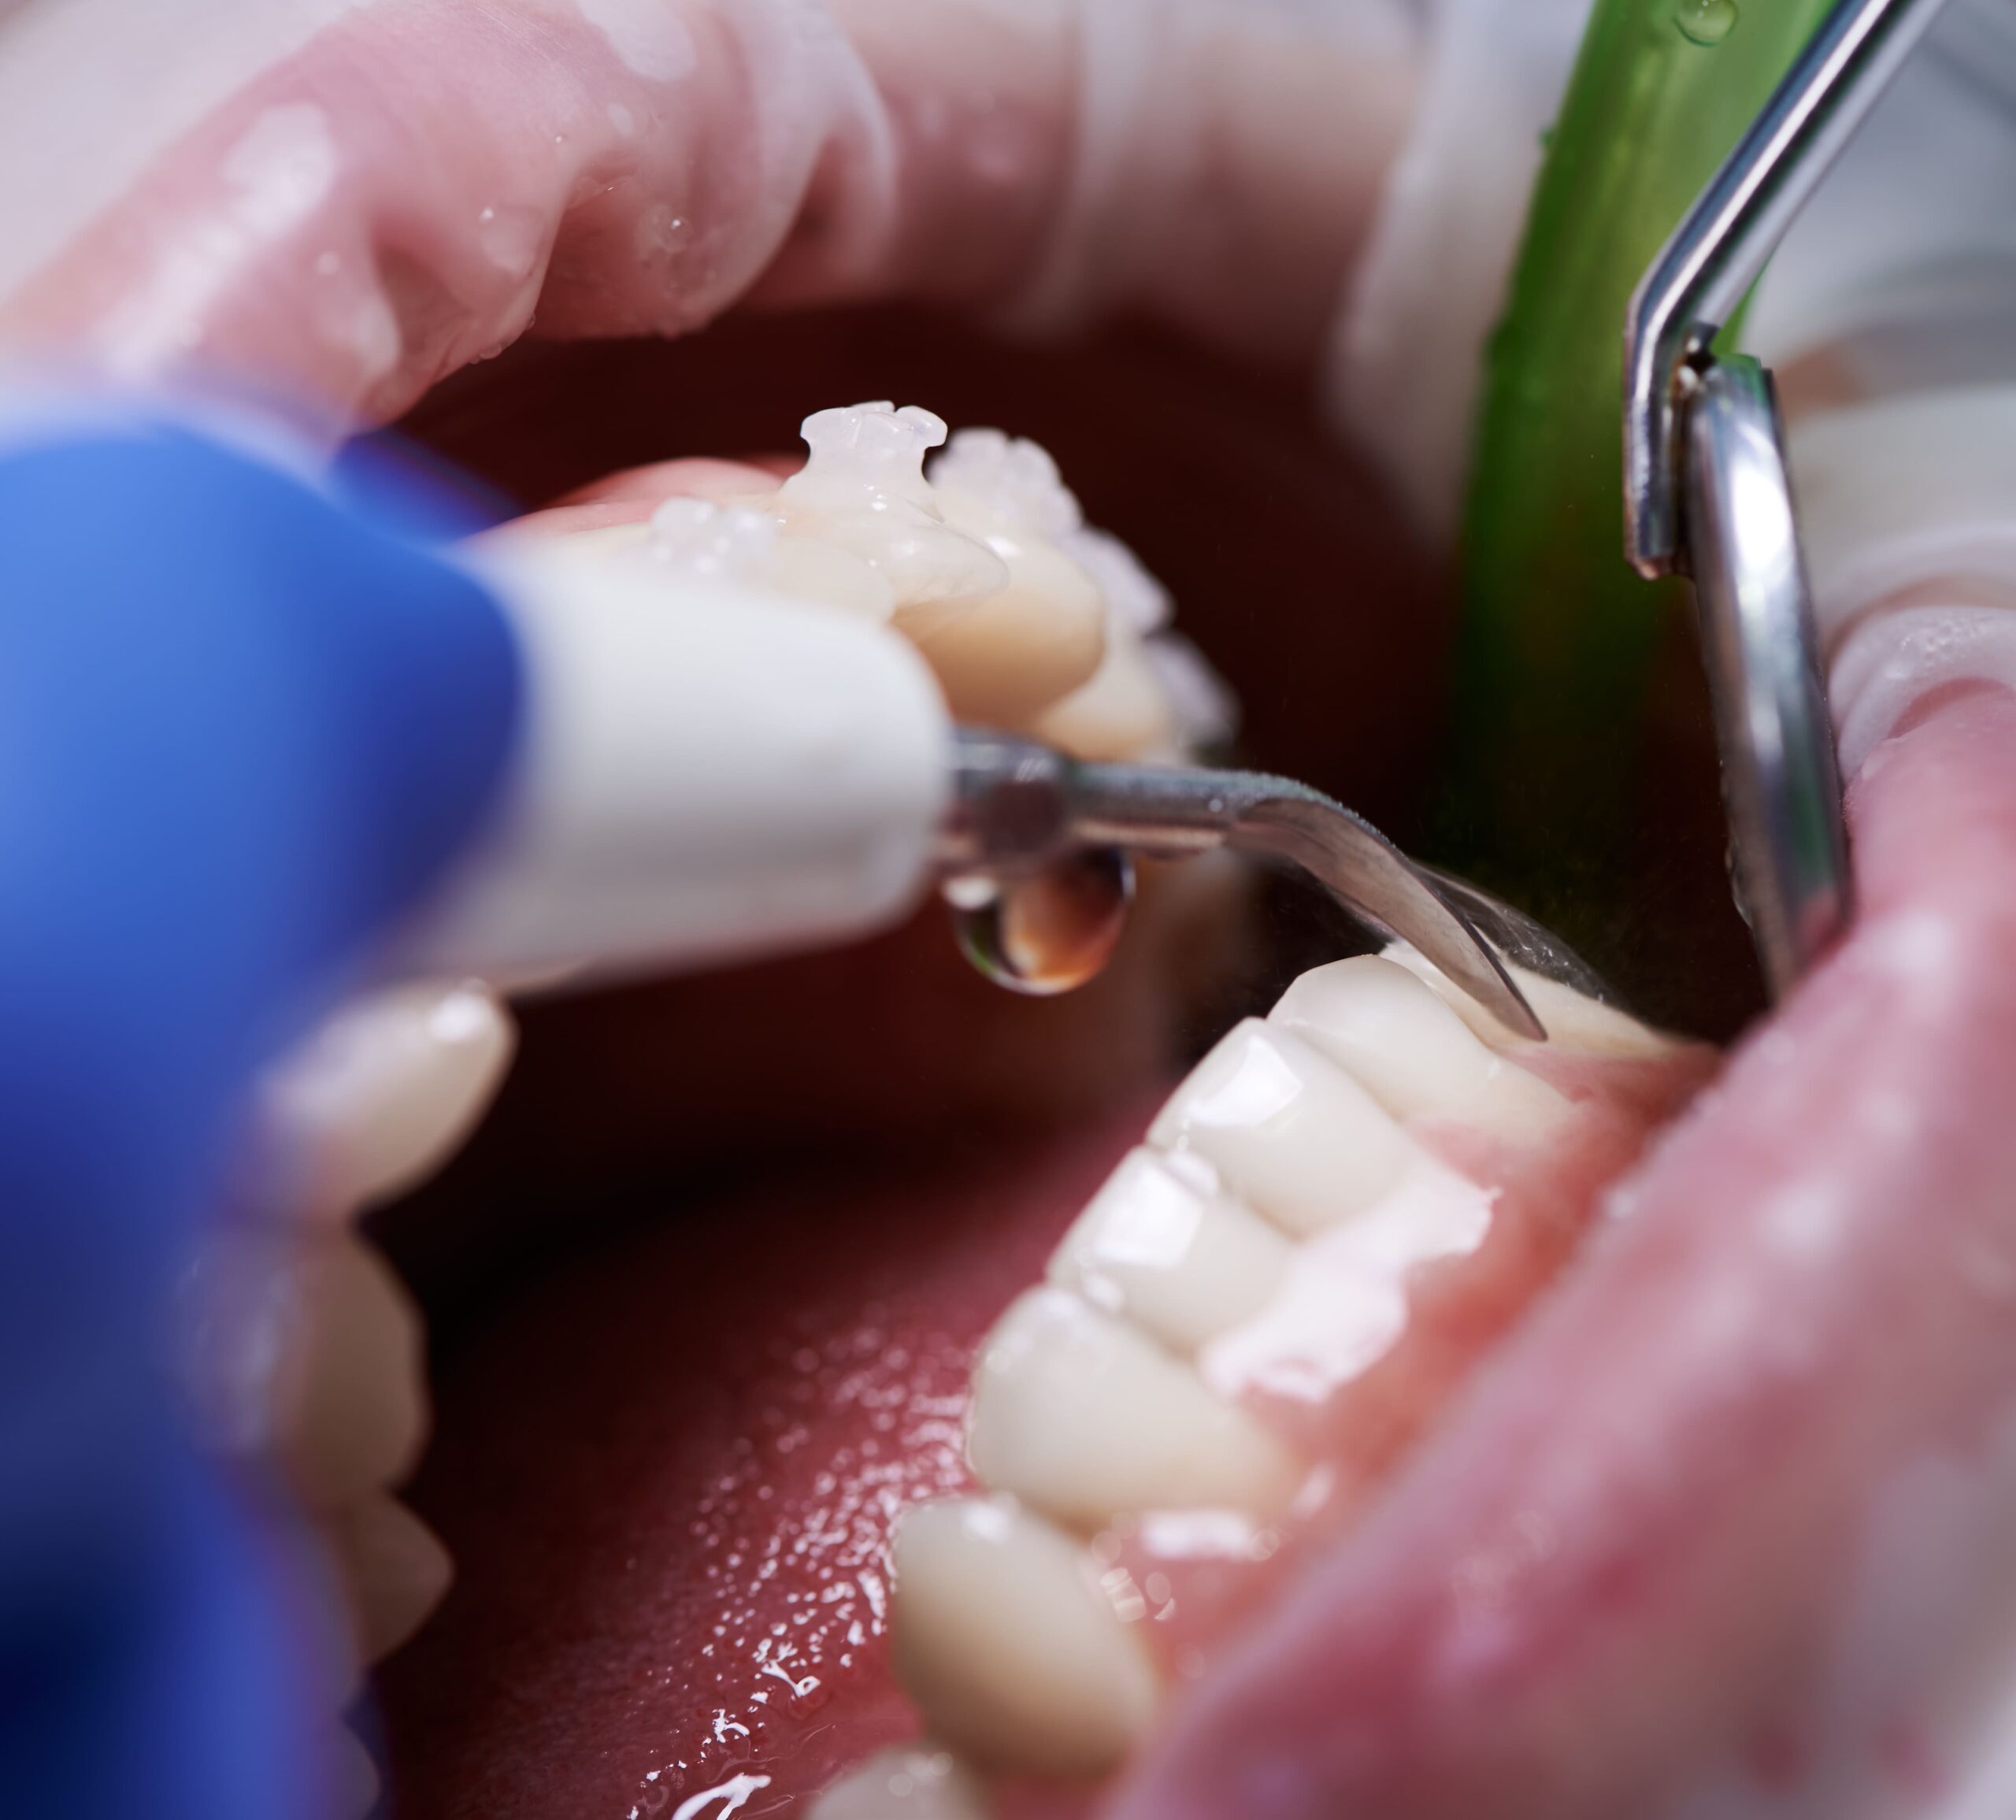

Dental Hygiene

Dental hygiene focuses on routine cleanings and preventive care to maintain healthy teeth and gums. Our hygienists customize each visit based on your periodontal health, using ultrasonic and hand scaling techniques, along with medicated gels or prescription rinses when needed, to ensure a comfortable and effective cleaning.